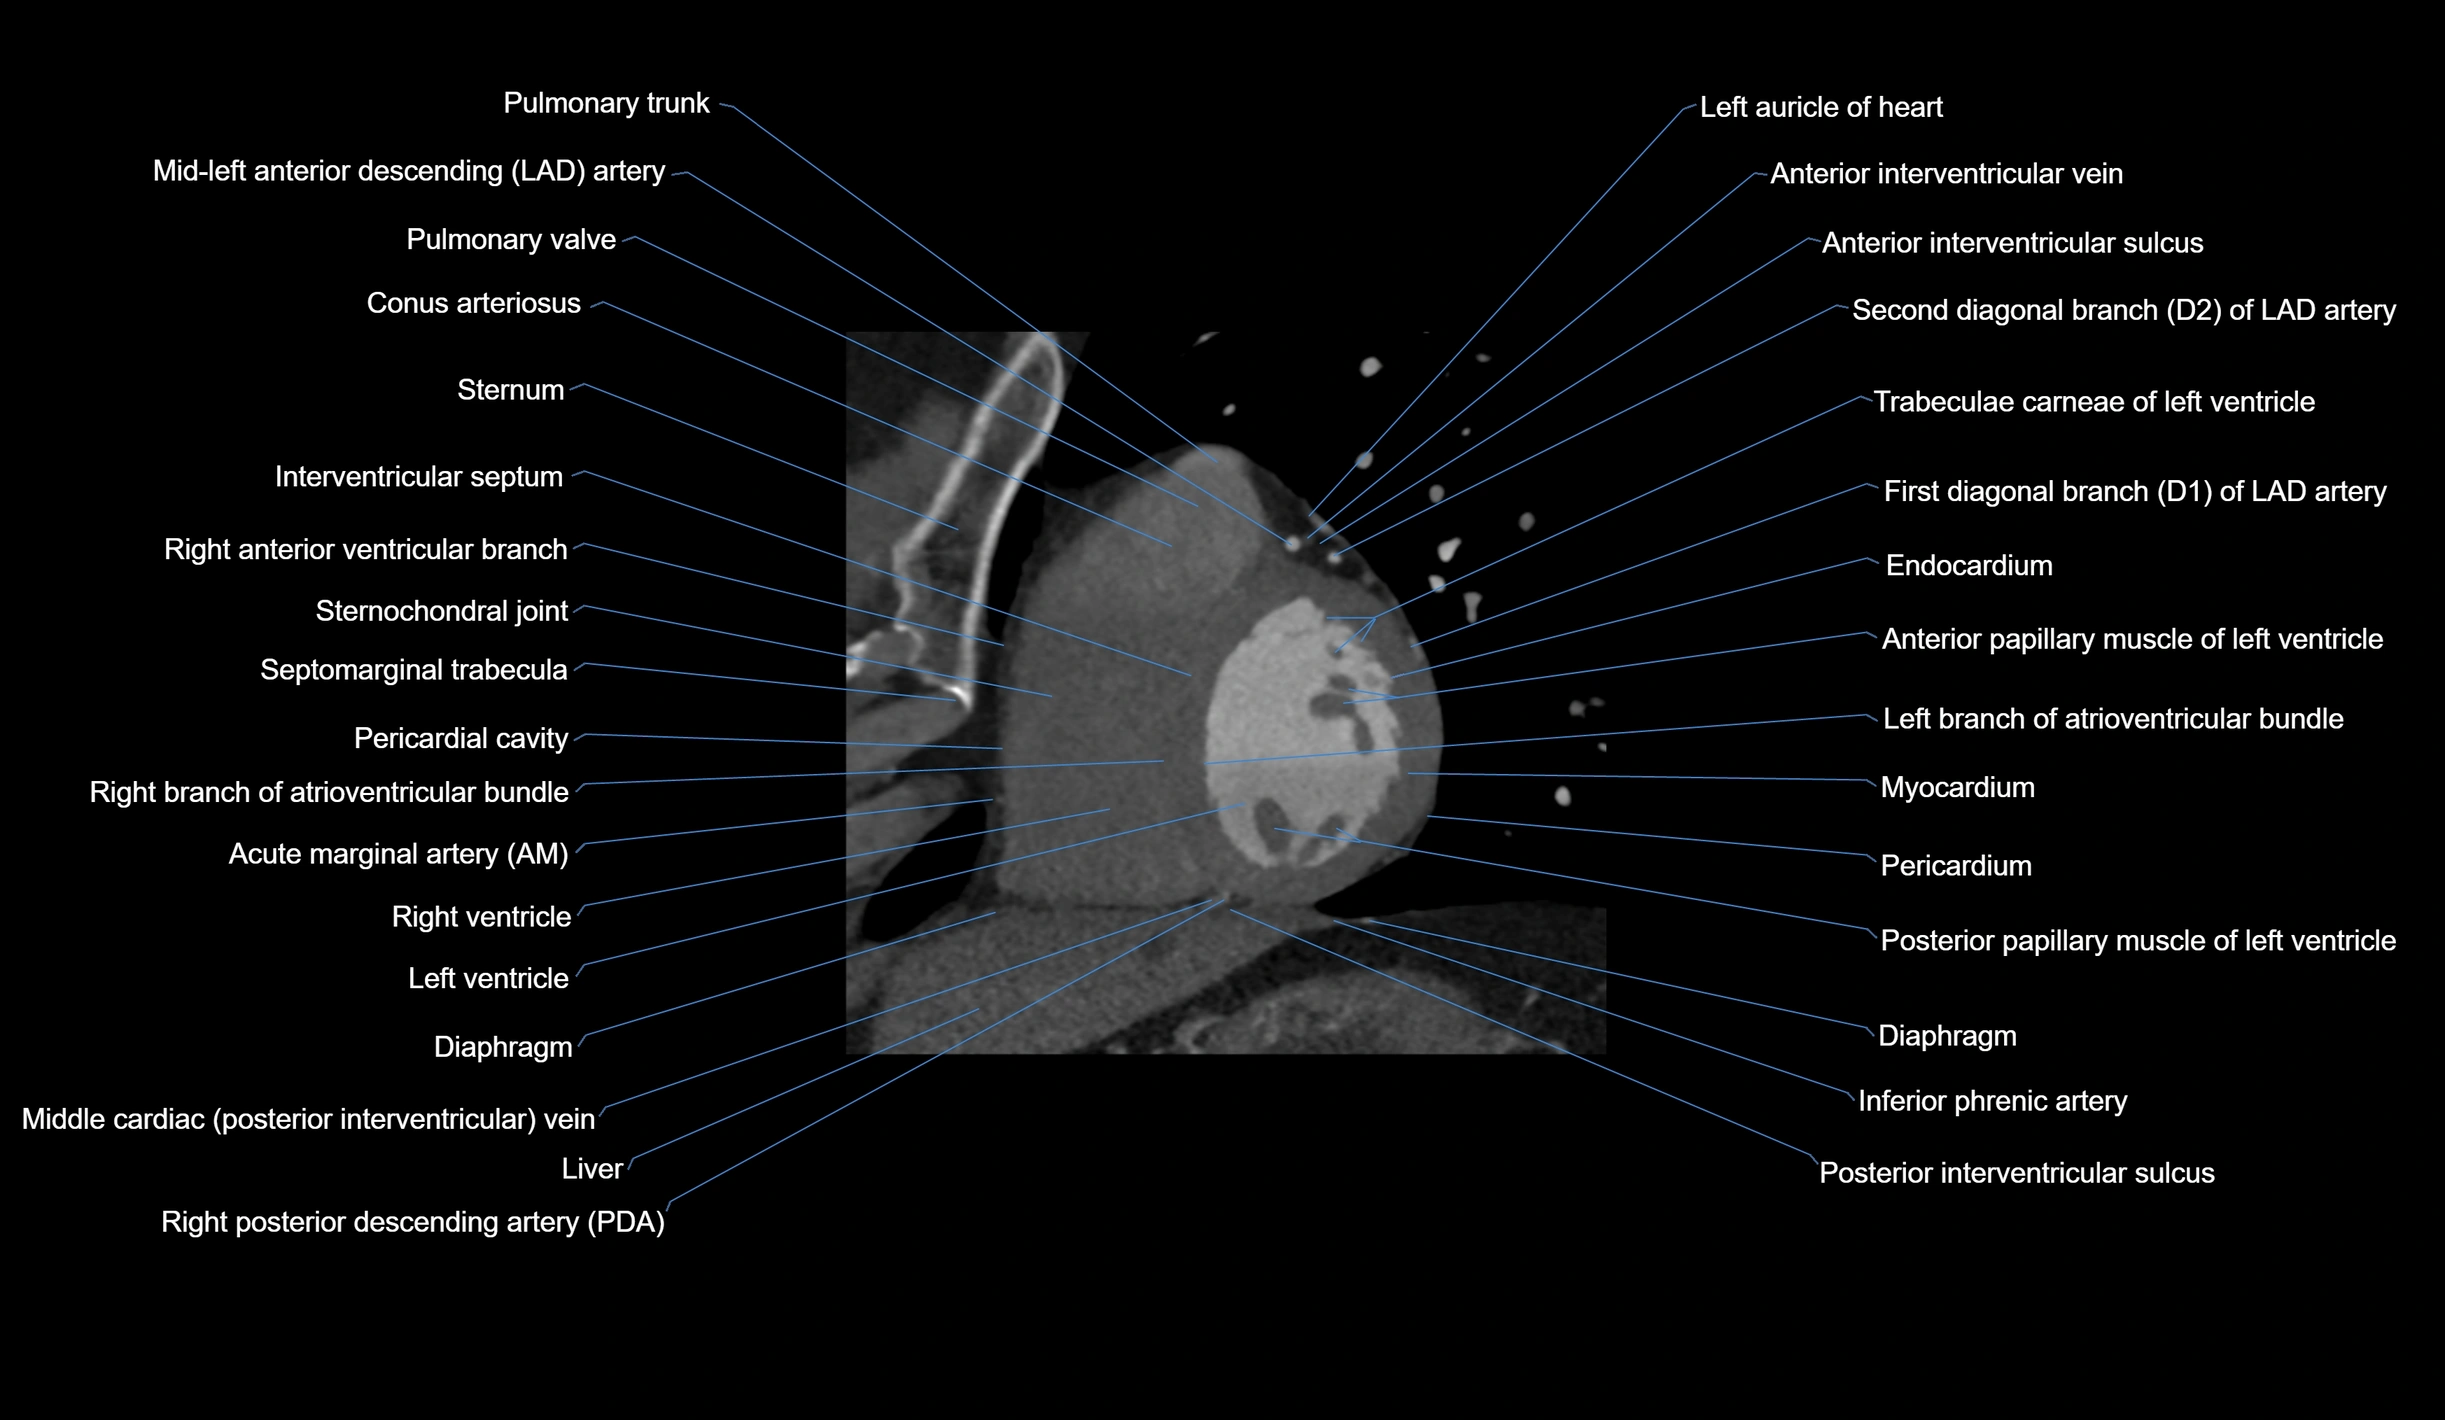

CT Coronary Angiography (CCTA):

Best non-invasive modality for acute marginal artery visualization

Shows origin, course along the acute margin, and right ventricular branches

Detects stenosis, occlusion, calcified and non-calcified plaques, aneurysm, or anomalous course

Multiplanar reformats and 3D reconstructions help in pre-PCI and surgical planning

Critical for assessing right ventricular infarction risk in RCA disease